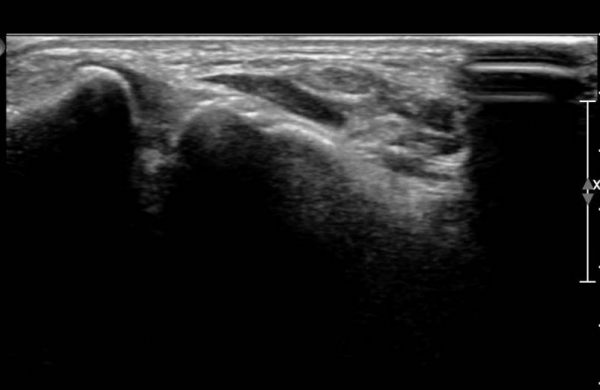

Àü°ÅºñÀδë,  Á¾°ñºñ°ñÀÎ´ë °Ë»ç»ó  ÀÌ»ó ¼Ò°ßÀ» º¸ÀÌÁö ¾ÊÀ½( »çÁø 5,  6)

¹Ý´ëÃø  ¾Õ°æ°ñºñ°ñÀδë Á¾´Ü¸é°Ë»ç¿¡¼­  Àδ밡  °í¿¡ÄÚ·Î Á¤»óÀûÀÎ ¸ð½ÀÀ» º¸ÀÓ(»çÁø 7).